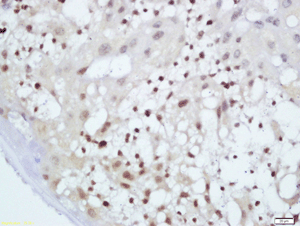

Clone number: polyclonal

isotype: rabbit polyclonal antibody

Cellular localization: nucleus/plasmid

Tissue: paraffin section

Positive Control: